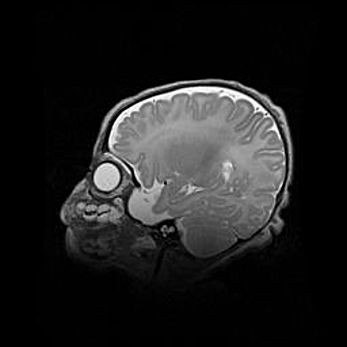

Наружная гидроцефалия с возможной атрофией височных областей.

Возраст: 28 дней

Вес: 3670 г

Пол: мужской

Окружность головы: 38 см

Срок гестации: 40 недель

Гидроцефалия головного мозга у новорожденных – это заболевание, которое характеризуется скоплением избыточного количества спинномозговой жидкости в желудочковой системе головного мозга в результате затруднения её перемещения от места выработки к месту поглощения в кровеносную систему или вследствие нарушения абсорбции. При открытой наружной форме гидроцефалии у новорожденных расширяются и переполняются субарахноидные пространства.

При нормотензивных  формах,  которые,  как  правило,  являются  следствием  перенесенных ишемических  повреждений  паренхимы  мозга,  возможно  сочетание микроцефалии  с нормотензивной гидроцефалией. В основе данных изменений лежит атрофия больших полушарий с преимущественной  локализацией  в  лобно-височных  областях.